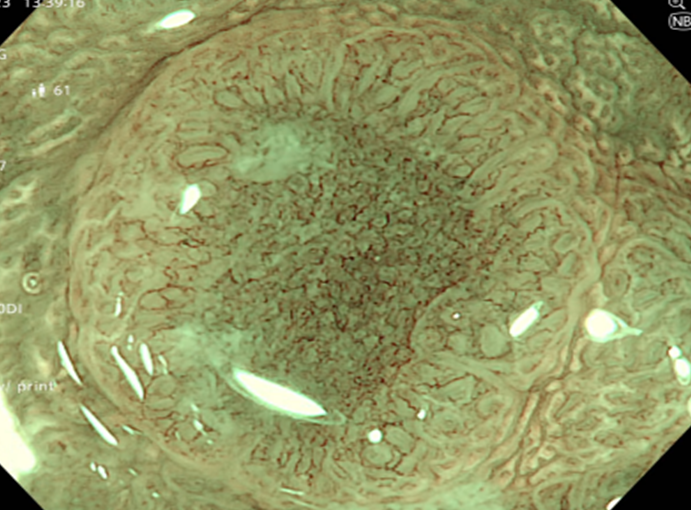

Kết quả nội soi dạ dày: Viêm teo niêm mạc dạ dày (C2 theo Kimura), dị sản ruột và có vi khuẩn H.pylori dương tính với test Urease từ mảnh sinh thiết qua nội soi.

Hình 1: Hình ảnh nội soi dạ dày

Kết quả nội soi đại tràng: có 3 polyp đại tràng (Paris Is, Kudo IIIL) (đã được cắt polyp qua nội soi), đại tràng sigmoid đã cắt một phần, tổn thương lồi đại trực tràng dạng polyp không cuống, ranh giới rõ, bề mặt màu hồng, có nhiều polyp có lớp nhầy ở trên bề mặt và thấy có hình ảnh da gà xung quanh tổn thương. Trên hình ảnh M-NBI thấy các tổn thương có các tuyến giãn nhẹ nhưng còn đều, mạch máu giãn nhẹ, chưa có biến đổi hình dạng --> đã tiến hành sinh thiết

Hình 2: Hình ảnh nội soi đại tràng